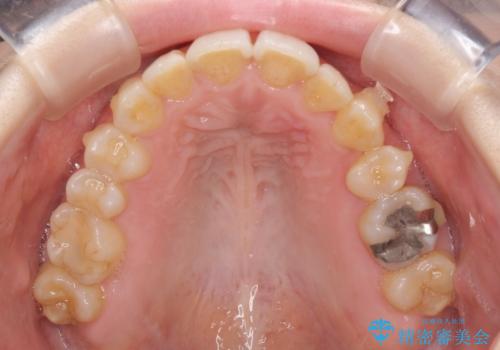

- 顕著な八重歯など、上下前歯のデコボコとスペースを気にして来院された患者様です。

八重歯改善には第一小臼歯の抜歯が必要であり、移動量が多いことから補助装置により八重歯を引き込むこととしました。

補助装置だけでなく、部分的にワイヤー矯正も使用しましたが、上下のスペースは改善しきれず、側切歯(前から2番目の歯)や顕著な八重歯は、インビザラインで治療するには限界があることがよく分かりました。

より良い仕上がりを希望される場合には、ワイヤー装置による矯正治療がお勧めとなります。